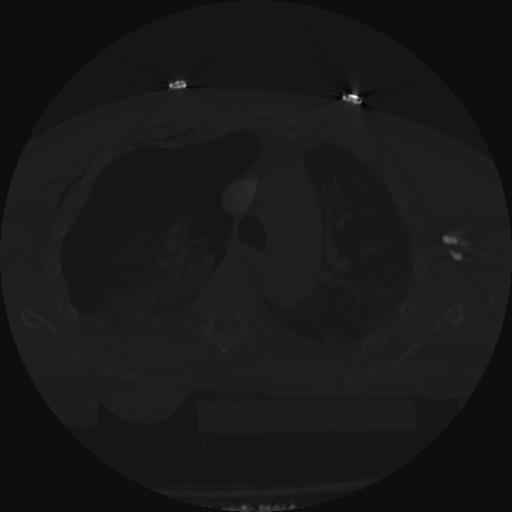

22 ANGIO,CE,Vol,0.5,ANGIO,,